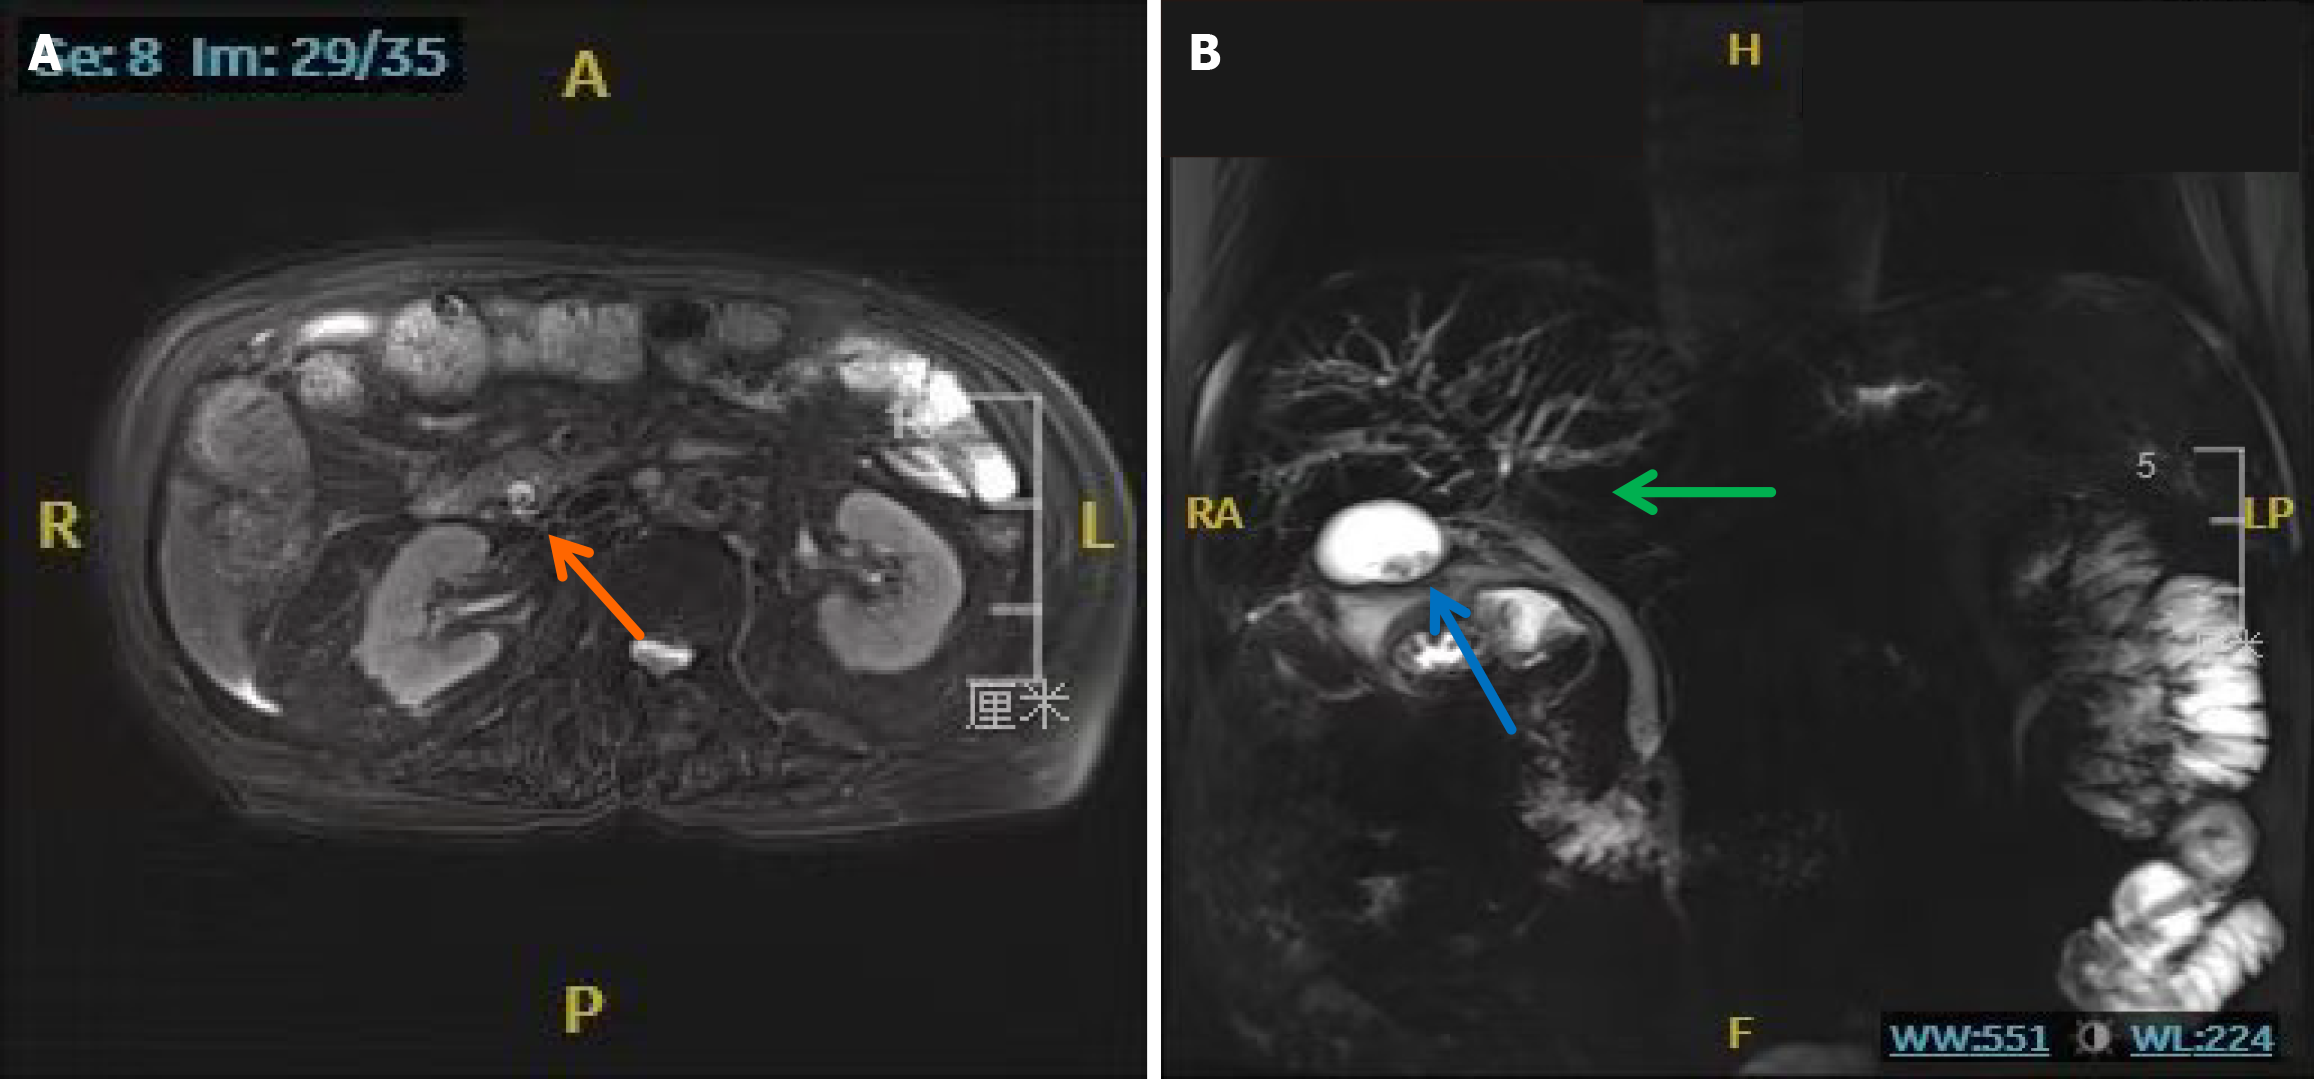

Figure 1 Abdominal computed tomography performed on June 27, 2024.

A: Common bile duct stone (orange arrow); B: Hazy peripancreatic fat stranding (green arrow).